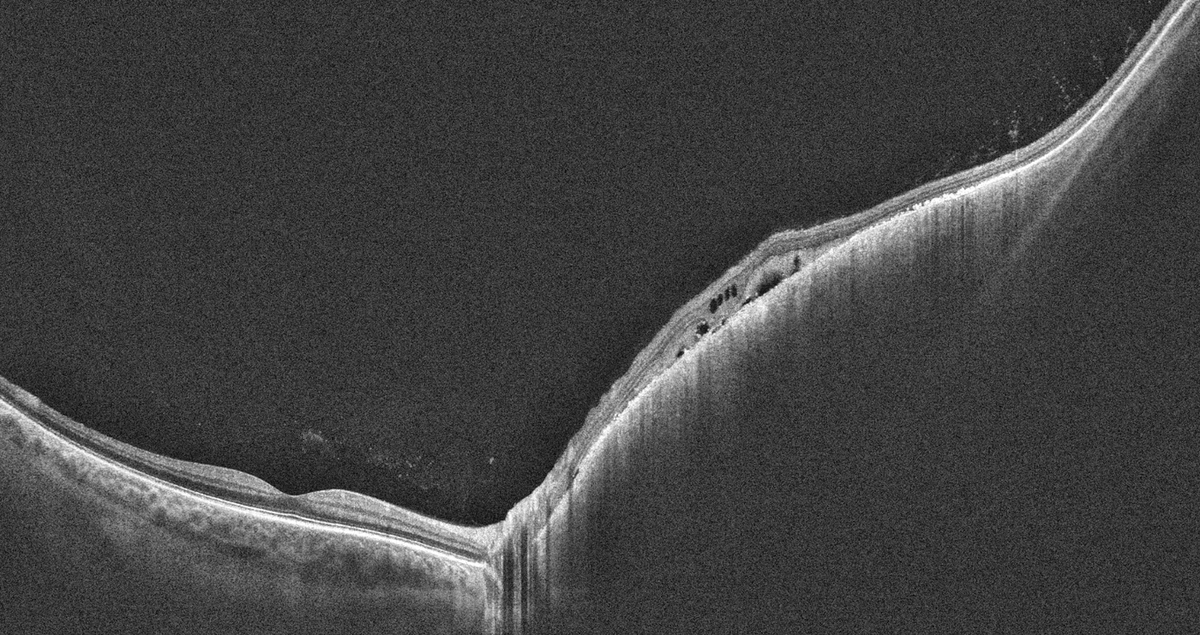

OCT Intalight montrant un épaississement choroïdien lié à un mélanome nasal avec fluide sous-rétinien

OCT Intalight — Épaississement choroïdien lié à un mélanome nasal (IPO Paris)

• OCT (Tomographie par Cohérence Optique) — visualise le fluide sous-rétinien, l'épaississement choroïdien, les altérations de l'épithélium pigmentaire

Le diagnostic du mélanome de la choroïde repose sur un faisceau d'arguments d'imagerie multimodale, sans recours systématique à la biopsie. L'échographie en mode B reste l'examen clé, mais l'OCT, l'OPTOS et l'IRM complètent le bilan diagnostique et pronostique.